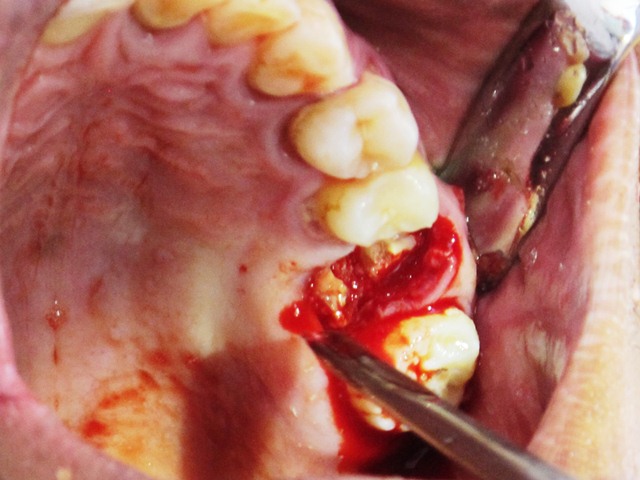

2013-13